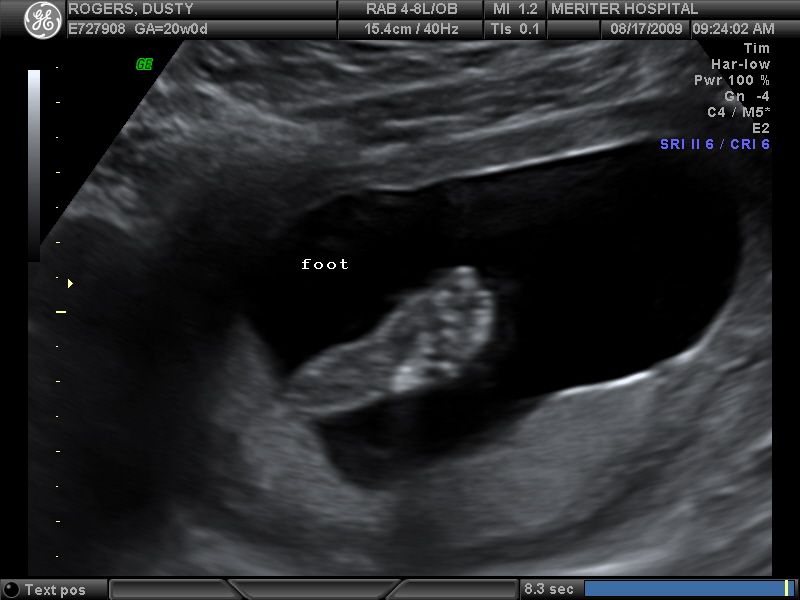

Check out that foot–it’s HUGE! No wonder I could feel her kicks so early in my pregnancy, lol! I’m not sure how zoomed in this picture is, but even the ultrasound technician commented on how big her feet are. I may have to hide my shoes sooner than I originally thought!